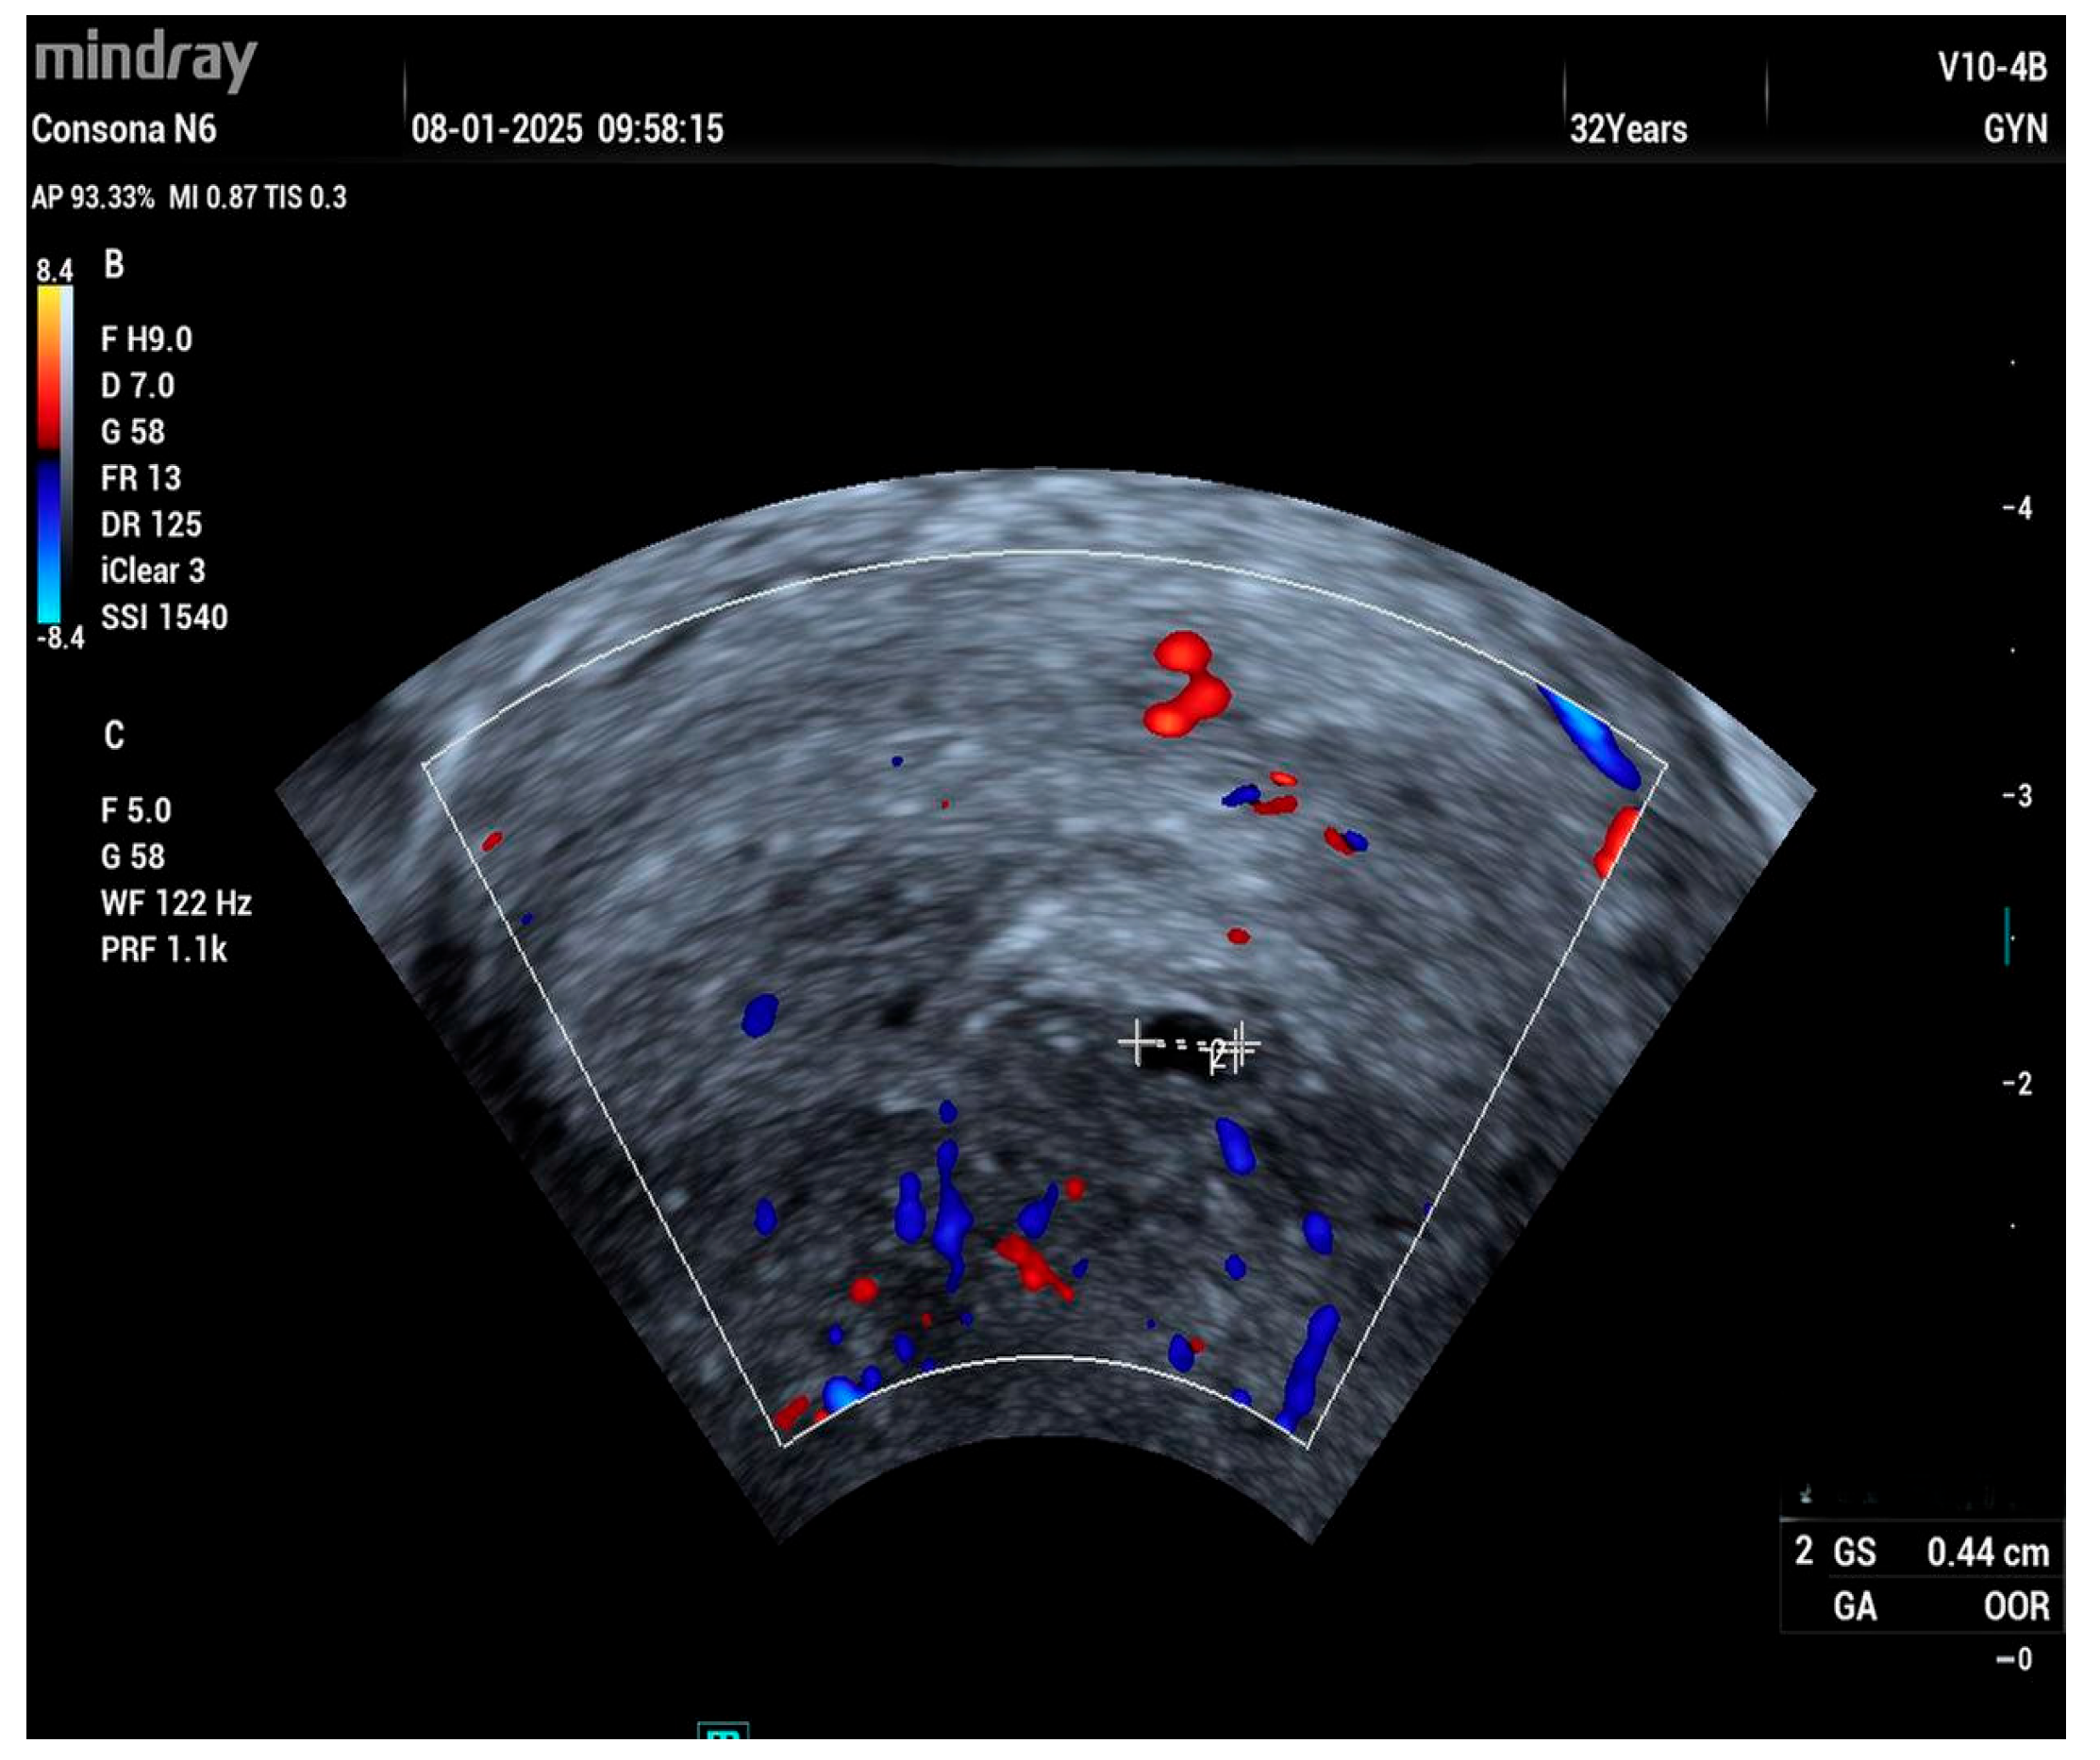

2. Case Report